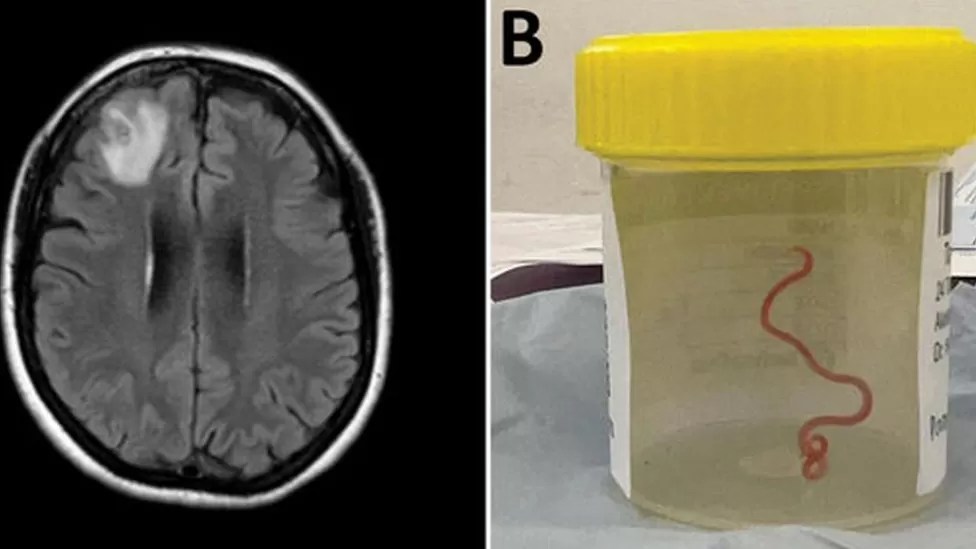

BREAKING: Live Worm Found In 64-Year-Old Australian Woman’s Brain In World First Discovery—In a world first, scientists say that an 8cm (3in) worm has been found alive in the brain of an Australian woman.

The “string-like structure” was pulled from the England-born patient’s damaged frontal lobe tissue during surgery in Canberra last year.

The red parasite could have been there for up to two months.

The patient was admitted to hospital in late January 2021. A scan later revealed “an atypical lesion within the right frontal lobe of the brain”. The cause of her condition was only revealed by a surgeon’s knife during a biopsy in June 2022.